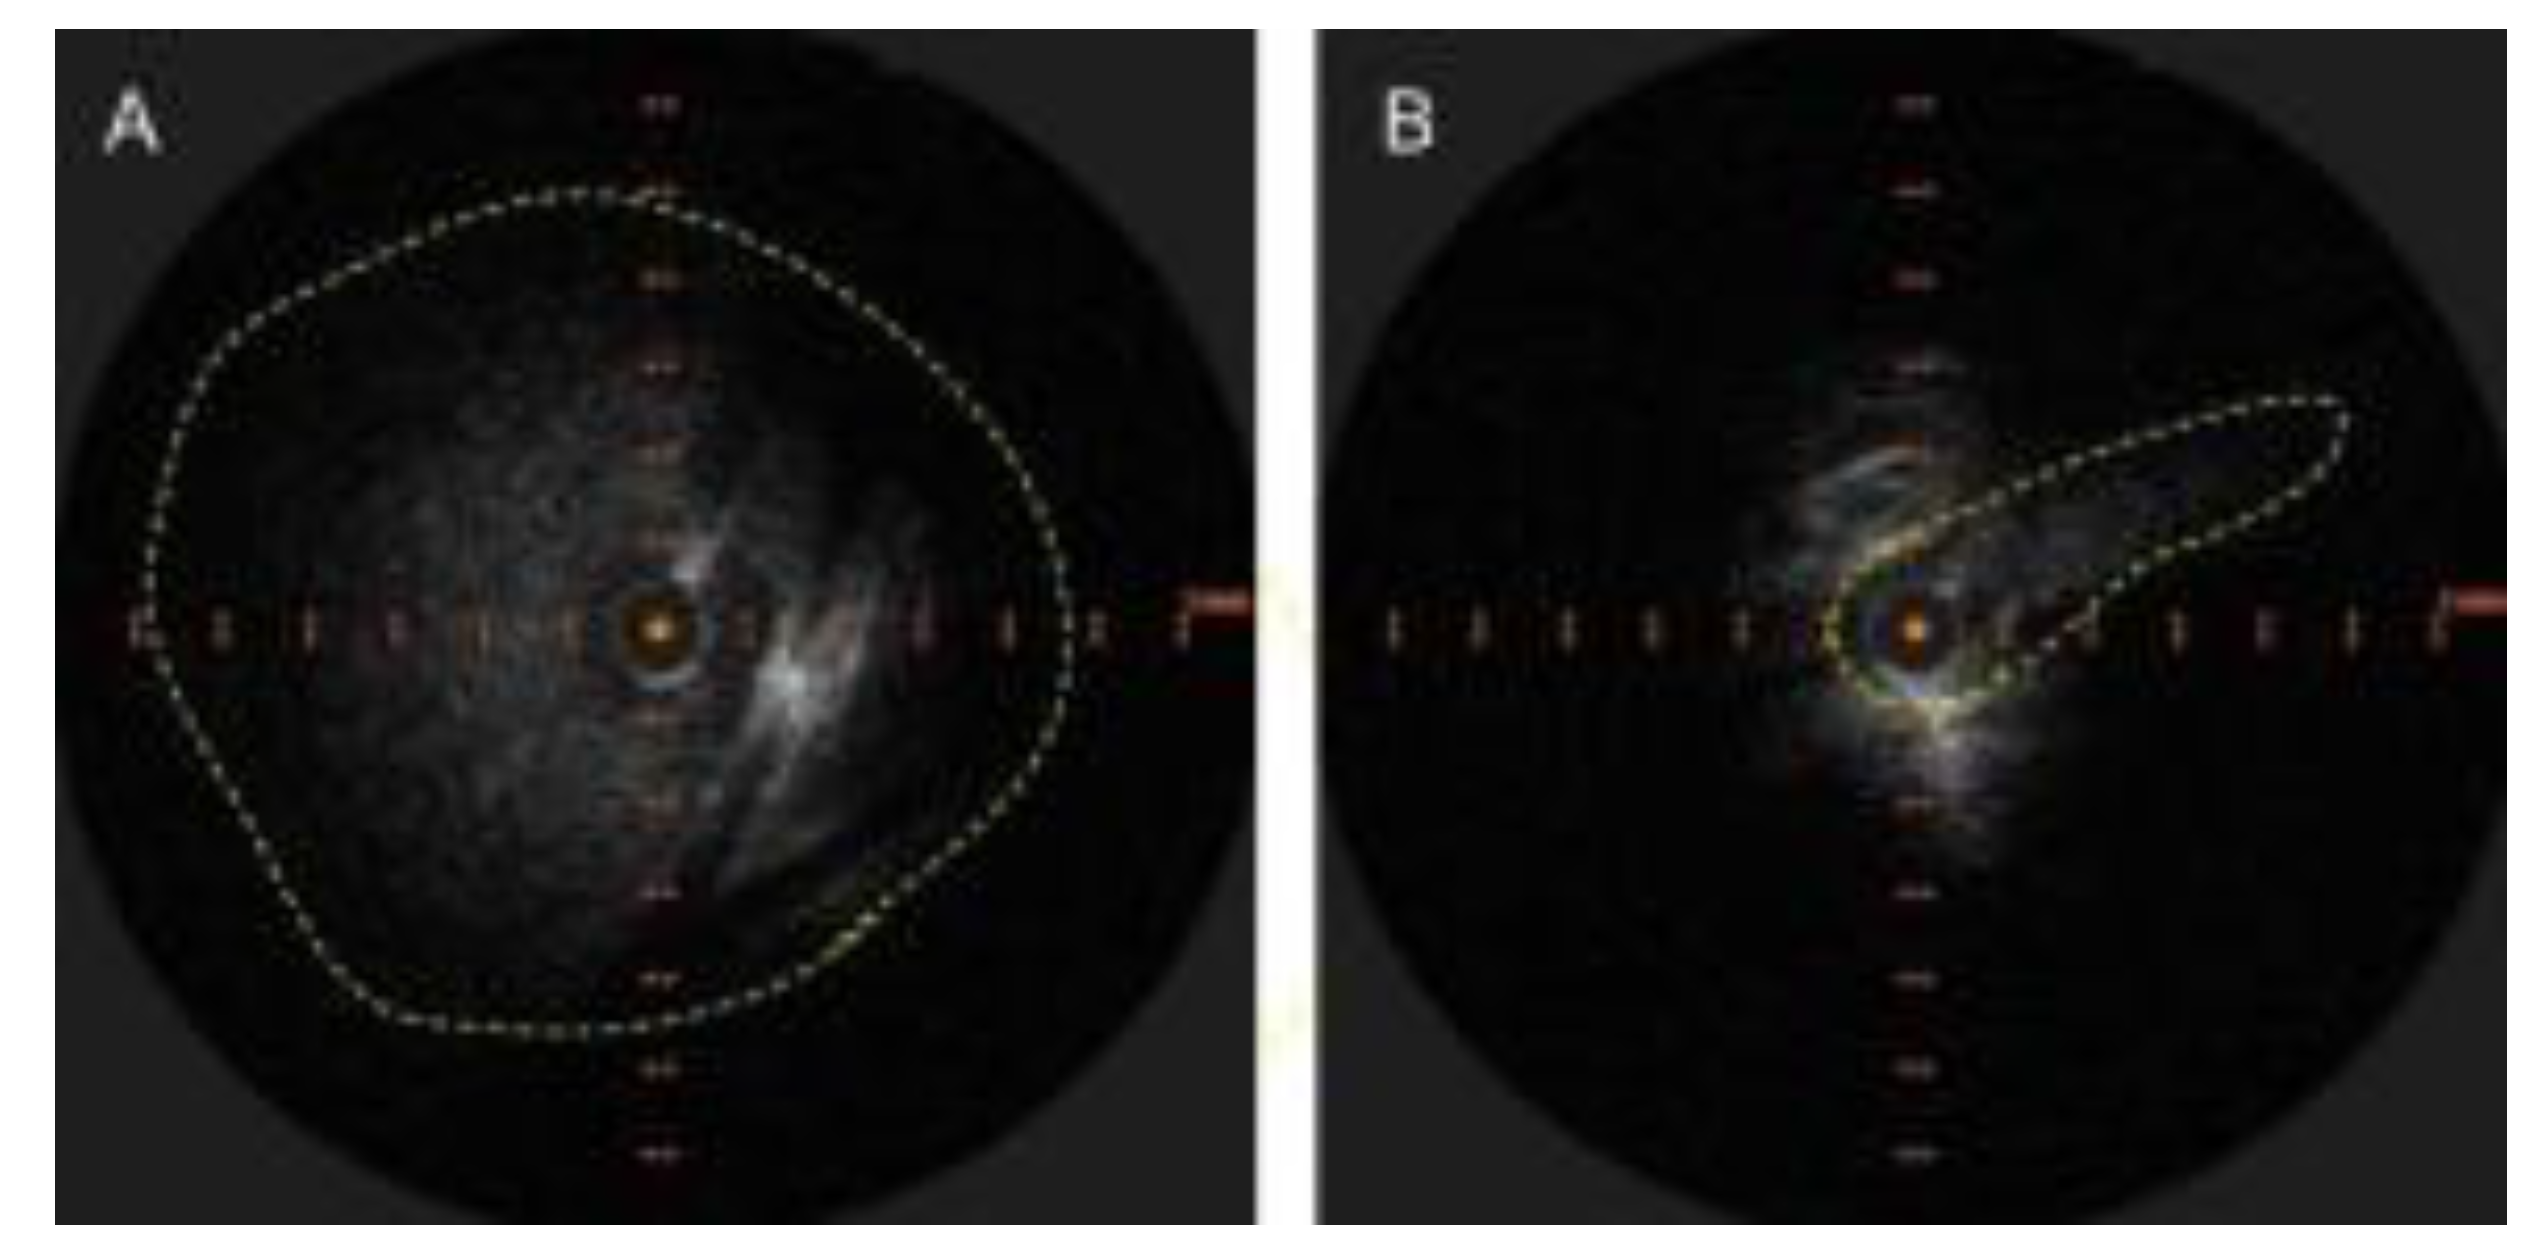

The radiological findings are often obvious but the apparent lack of clinical relevance lends to underreporting. As an example, osteoporotic vertebral fractures suffer a similar fate [8]. There are excellent examples of LBV compression with resultant venous reflux on CT angiography [9,10]. Similar findings are noted on MR Venography [11]. However, this condition will continue to elude detection by CT angiography, if right sided injections are performed [10] and MR venography of the neck if coverage does not extend down to the level of the LBV. Intravascular ultrasound (IVUS) should be the new "gold standard" for diagnosis as it clearly identifies and demonstrates the dramatic decrease in luminal area while providing accurate vessel measurements that are necessary for treatment.

Figure 1. A. Appearance of LBV on intravascular ultrasound with manual demarcation of approximate border with dashed yellow lines B. Severe slit like compression of LBV.